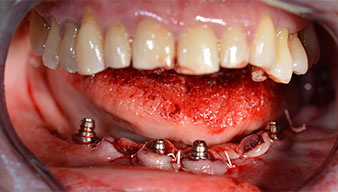

A three-dimensional cone beam computed tomography scan (CBCT, Planmeca) was performed to aid planning and minimize risks. This revealed that the quality and quantity of the available bone were sufficient for the surgery and immediate restoration using the Fast & Fixed method. Following the protocol for this concept, the implants are inserted at 35, 32, 42 and 45. Angling the distal implants by up to 45° shifts the emergence profile to posterior and generates a larger support polygon (Fig. 3).

Fast & Fixed method

Fig. 3